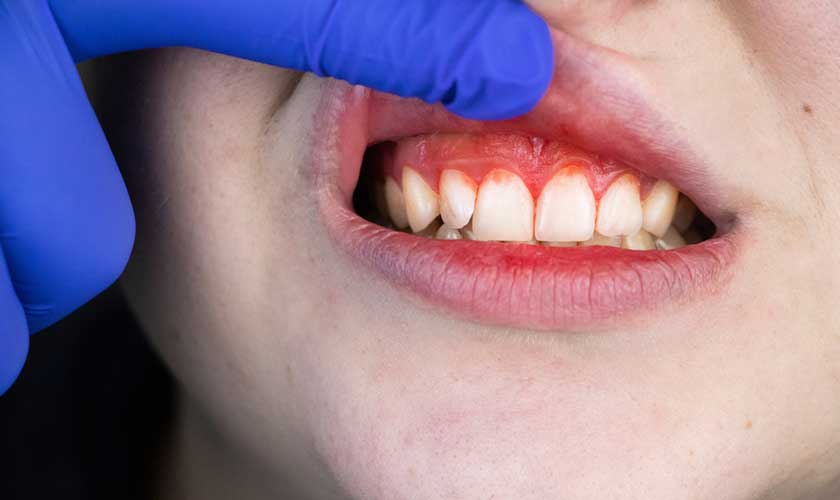

Theo thời gian, nướu bị viêm sẽ bị sưng và dễ chảy máu. Sâu răng (sâu răng) cũng có thể xảy ra. Nếu không được điều trị, viêm nướu có thể tiến triển thành viêm nha chu và cuối cùng là mất răng.

Vôi răng là nguyên nhân chính gây viêm nướu